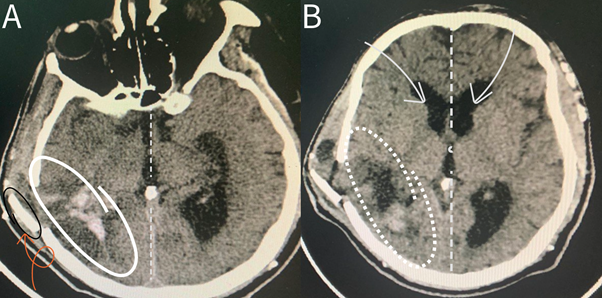

Following the successful evacuation of the intraparenchymal hematoma and the alleviation of elevated intracranial pressure, a Postoperative non-contrast brain CT scan showed significant improvement and no residual hemorrhage or pressure effect could be seen (Figure 2). An important aspect of the procedure involved the thoughtful repositioning of the previously removed bone flap. This restorative step was undertaken with extreme precision, considering both structural integrity and the capacity for physiological expansion within the cranial vault. The bone flap was carefully secured in a manner that not only provided protection to the vital neural structures beneath but also allowed for the accommodation of normal physiological processes and fluctuations within the intracranial environment. The surgery went smoothly, even though the bone flap moved because of the ongoing high pressure inside the skull.

Figure 2 Postoperative non-contrast brain CT scan showing the region where the previous hemorrhage occurred, with a noticeable return to the normal midline position of brain structures. (A) Lower brain section CT scan with notable return to midline (dashed line), and a clearly seen bone flap (orange curved arrow). (B) Upper brain section CT scan showing normal position f midline structures.